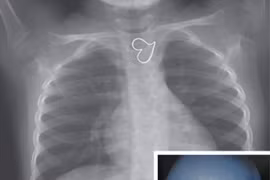

(GLO)- Tâm lý ngại đến bệnh viện, điều kiện kinh tế khó khăn, xa cơ sở y tế...nên nhiều người dân ở Gia Lai không chủ động khám sàng lọc bệnh lao. Vì vậy khi phát hiện bệnh đa phần đều ở giai đoạn muộn khiến việc điều trị gặp nhiều khó khăn.